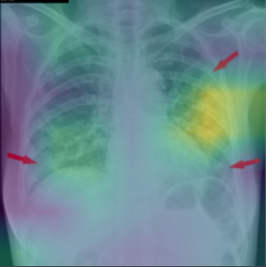

The third example, in Figure 5c), visualization is not clear. The study describes a different XAI method than the one present in the image. Moreover, this visualization highlights the whole image, and it is not possible to guess which features took part in the prediction. It is important to point out that some explanation methods can give clearer results for a specific type of DNN and for a specific domain.